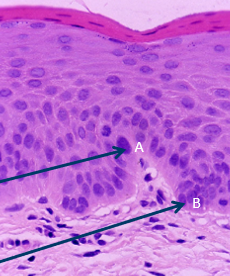

What do points A and B indicate? Describe the dysplasia of this tissue.

A

A = Pleomorphism/hyperchromatisism

B = Basal cell hyperplasia

Architecture changes confined to lower third, indicating mild dysplasia. Cell atypia is mild.